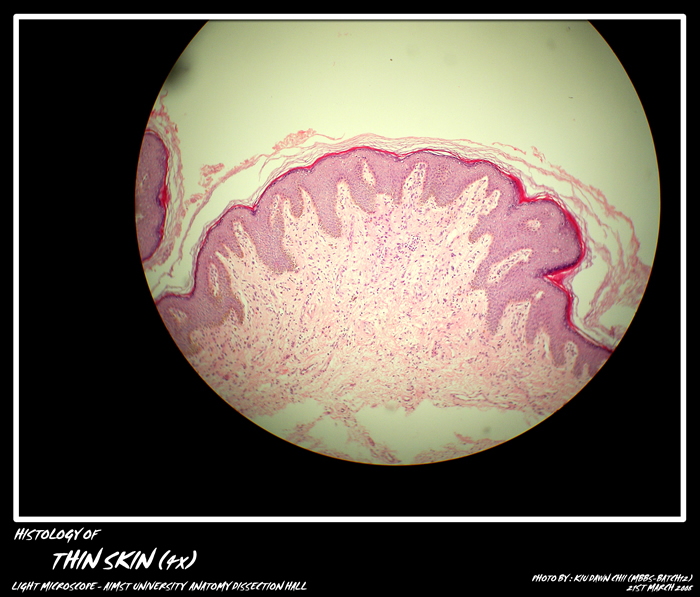

EPITHELIUM